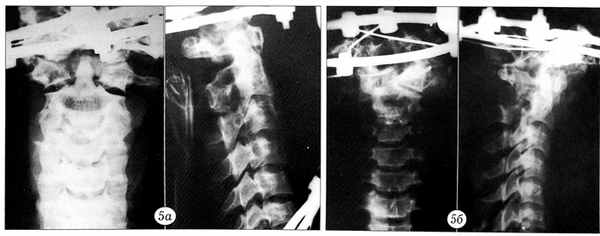

Результаты нагрузочного теста документировались графически. По оси ординат регистрировалось усилие в ньютонах, по оси абцисс — степень смещения позвонков в миллиметрах (рис. 2). При этом основное внимание уделялось величине нагрузки, при которой происходило наибольшее смещение позвонков. До и после нагрузочного теста производилась рентгенография блоков (рис. 3~5).

Рис. 5. Перелом Джефферсона до (а) и после (б) нагрузочного теста. На рентгенограмме в боковой проекции после нагрузки видно расширение щели сустава Крювелье.